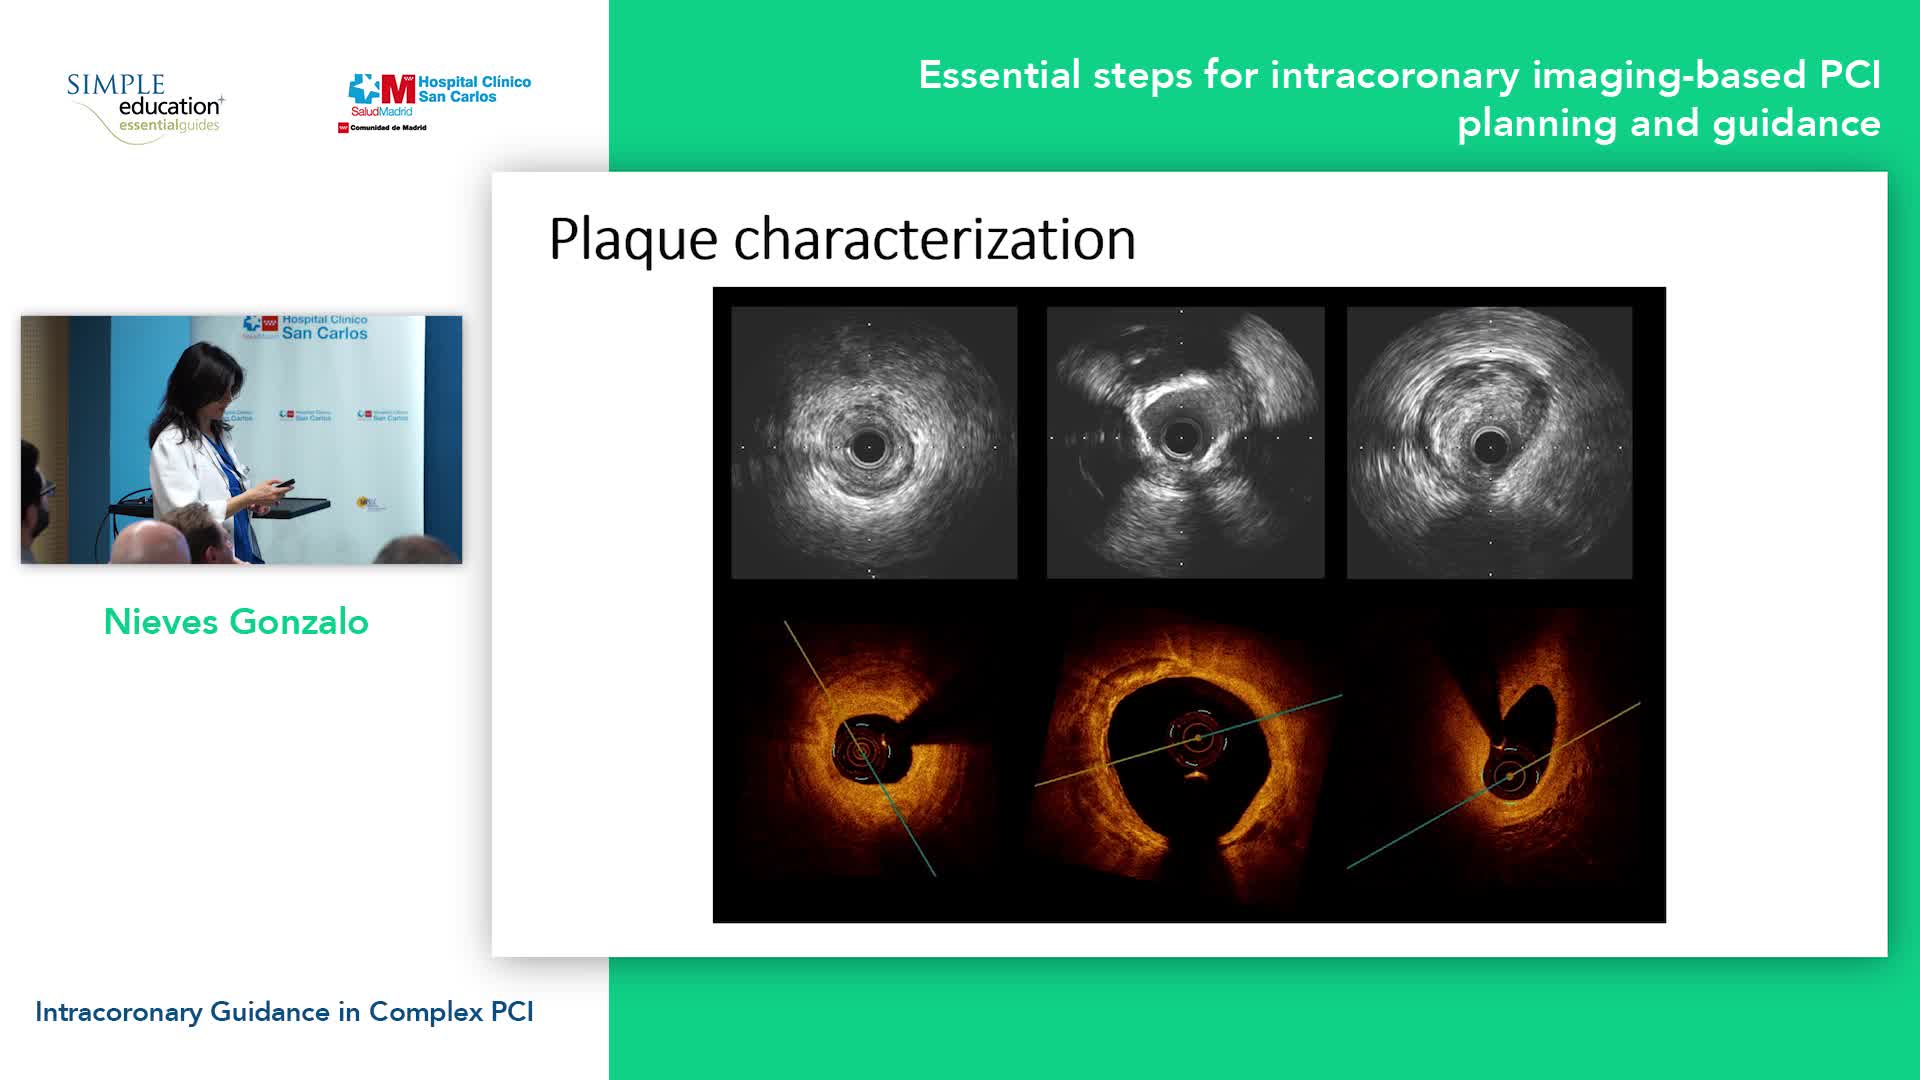

Advanced PCI Course Content

Essential steps for physiology-based PCI planning and guidance - Dr Allen Jeremias

Intracoronary guidance in acute coronary syndromes - Dr Hernan Mejia-Renteria